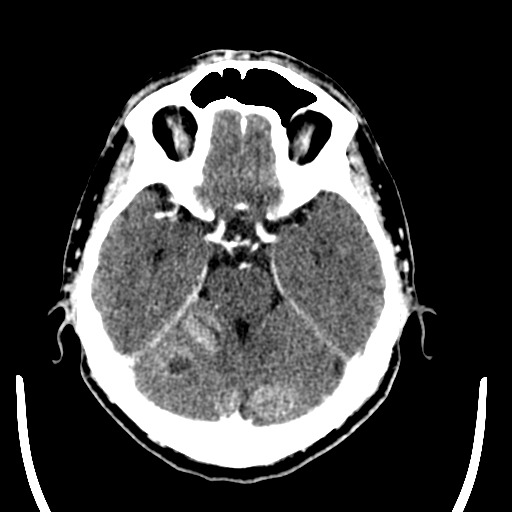

Пациент 53 лет поступил в терапевтическое отделение по ИБС, беспокоил кашель, на ОКГ деструктивная правосторонняя нижнедолевая пневмония. Выдал Джексоновскмие судороги, проведено СКТ головного мозга, после с контрастированием, выявлены кольцевидные тени с участками распада. Направлен на КТ дообследование легких

КТ-признаки периферического образования S9-10 правого легкого с признаками централизации, вторичными изменениями субкаринальных и правых бронхопульмональных лимфозлов, обтурационным субсегментарным бронхиолитом, гиповентиляцией нижней доли правого легкого. Вторичное поражение?левого надпочечника. Подозрение на единичный вторичный очаг верхней доли правого легкого. Мтс передней грудной стенки слева. Метастатическое поражение головного мозга с незначительным  перифокальным отеком.

Больной направлен в ООД на консультацию для подтверждения диагноза.